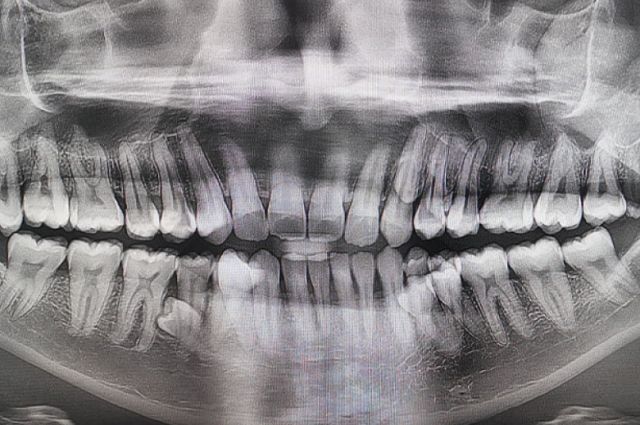

Мужчина обнаружил у себя «лишние» зубы случайно во время семейного чаепития. Обследование показало, что их на 10 больше нормы, причем растут они в два ряда. Два скрытых зуба врачи нашли только на рентгене, что официально сделало мужчину мировым рекордсменом.